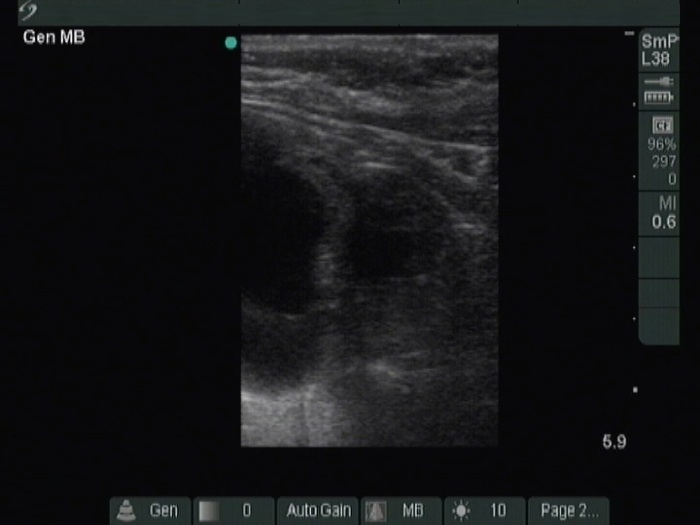

Ultrasonography. The thyroid was moderately hypoechoic. A large cystic nodule occupied great part of the right lobe. There was a moderately hypoechoic solid nodule in the lower third of the right lobe. This lesion presented with taller-than-wide and taller-than-long shape and had both perinodular and intranodular vascularity.

FNA of the solid nodule in the lower third of the right lobe resulted in oxyphilic cell tumor.

Histopathology disclosed oxyphilic variant of a minimally invasive follicular carcinoma in the suspicious nodule. The other nodules proved to be hyperplastic nodules.